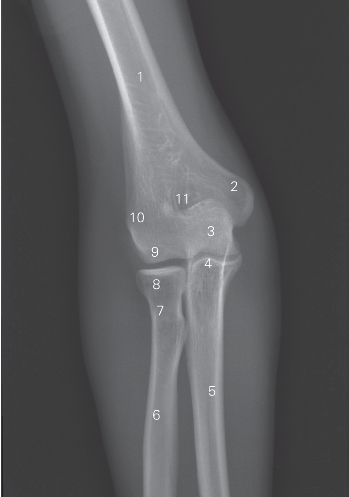

图7-2 肘关节正位DR平片

1 肱骨 humerus 2 内上髁 medial epicondyle

3 肱骨滑车trochlea of humerus 4 尺骨冠突 coronoid process of ulna

5 尺骨 ulna 6 桡骨 radius

7 桡骨颈 neck of radius 8 桡骨小头 capitulum radii

9 肱骨小头 capitulum humeri 10 外上髁 lateral epicondyle

11 鹰嘴窝 olecranon fossa